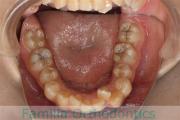

No.22V-029

- 主な症状:

- 叢生

- その他の症状:

- 上顎前突

- 年齢:

- 19歳

- 性別:

- 男性

- 抜歯部位

- 上:

- 8448

- 下:

- 主な使用装置:

- FEA 022

- 治療にかかった費用:

- 92万円

でこぼこを治したいということで来院されました。上下左右から親知らずも第一小臼歯も抜歯が必要で、歯科矯正アンカースクリューを併用して大臼歯を後ろに引っ張りながらの治療でした。3年弱、35回程度の通院が必要でした。

叢生が著しく、後戻りのリスクがあります。またアンカースクリューが必須のため、もしもスクリューが安定しないと、治療が難しく長くなってしまう恐れがありましたが、幸い脱落は見られませんでした。